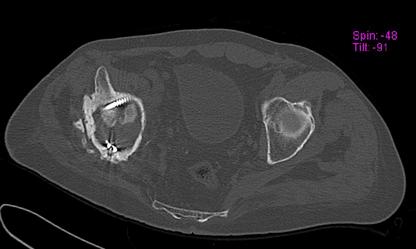

Пациент 49 лет, паровозная травма 23.2.2006, получил вертикальная

нестабильное повреждение таза, разрыв левого крестцово-подвздошного

сочленения, перелом лонной, седалищной костей слева, T-образный

оскольчатый перелом правой вертлужной впадины с переломом заднего

края, вывих правого бедра, посттравматическая пояснично-крестцовая

плексопатия с обеих сторон, паралич мышц правой голени.

В день травмы - вправление вывиха, скелетное вытяжение, 14.3.2006

чрескостный остеосинтез таза. 20.4.2006 остеосинтез правой вертлужной

впадины пластинами, осложнившийся нагноением межмышечной гематомы

правой ягодичной области. Получал консервативное лечение, было

достигнуто полное заживление раны. 24.7.2006 введены илиосакральные

винты слева. С декабря 2006 года и по настоящее время ходит на

костылях без опоры на правую ногу. Планируется THA. Помогите

определиться с вариантом костной пластики? И какую укрепляющую

конструкцию использовать?